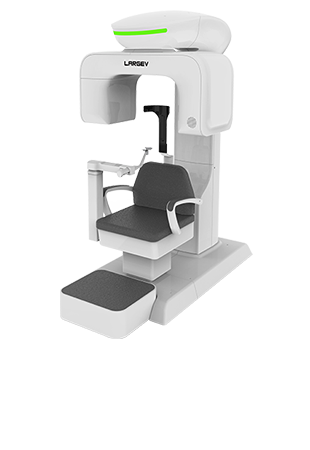

LargeV Instrument Corp., Ltd., fondée en 2011, se distingue par son expertise dans la conception et la fabrication d’équipements médicaux de haute qualité, notamment dans le domaine du CBCT dentaire, de l’imagerie dentaire et de la radiologie orthodontique. Soutenue par une équipe technique issue de l’Université de Tsinghua, elle met l’accent sur l’innovation et la qualité. Récemment, plusieurs de ses produits ont obtenu la certification européenne MDR.